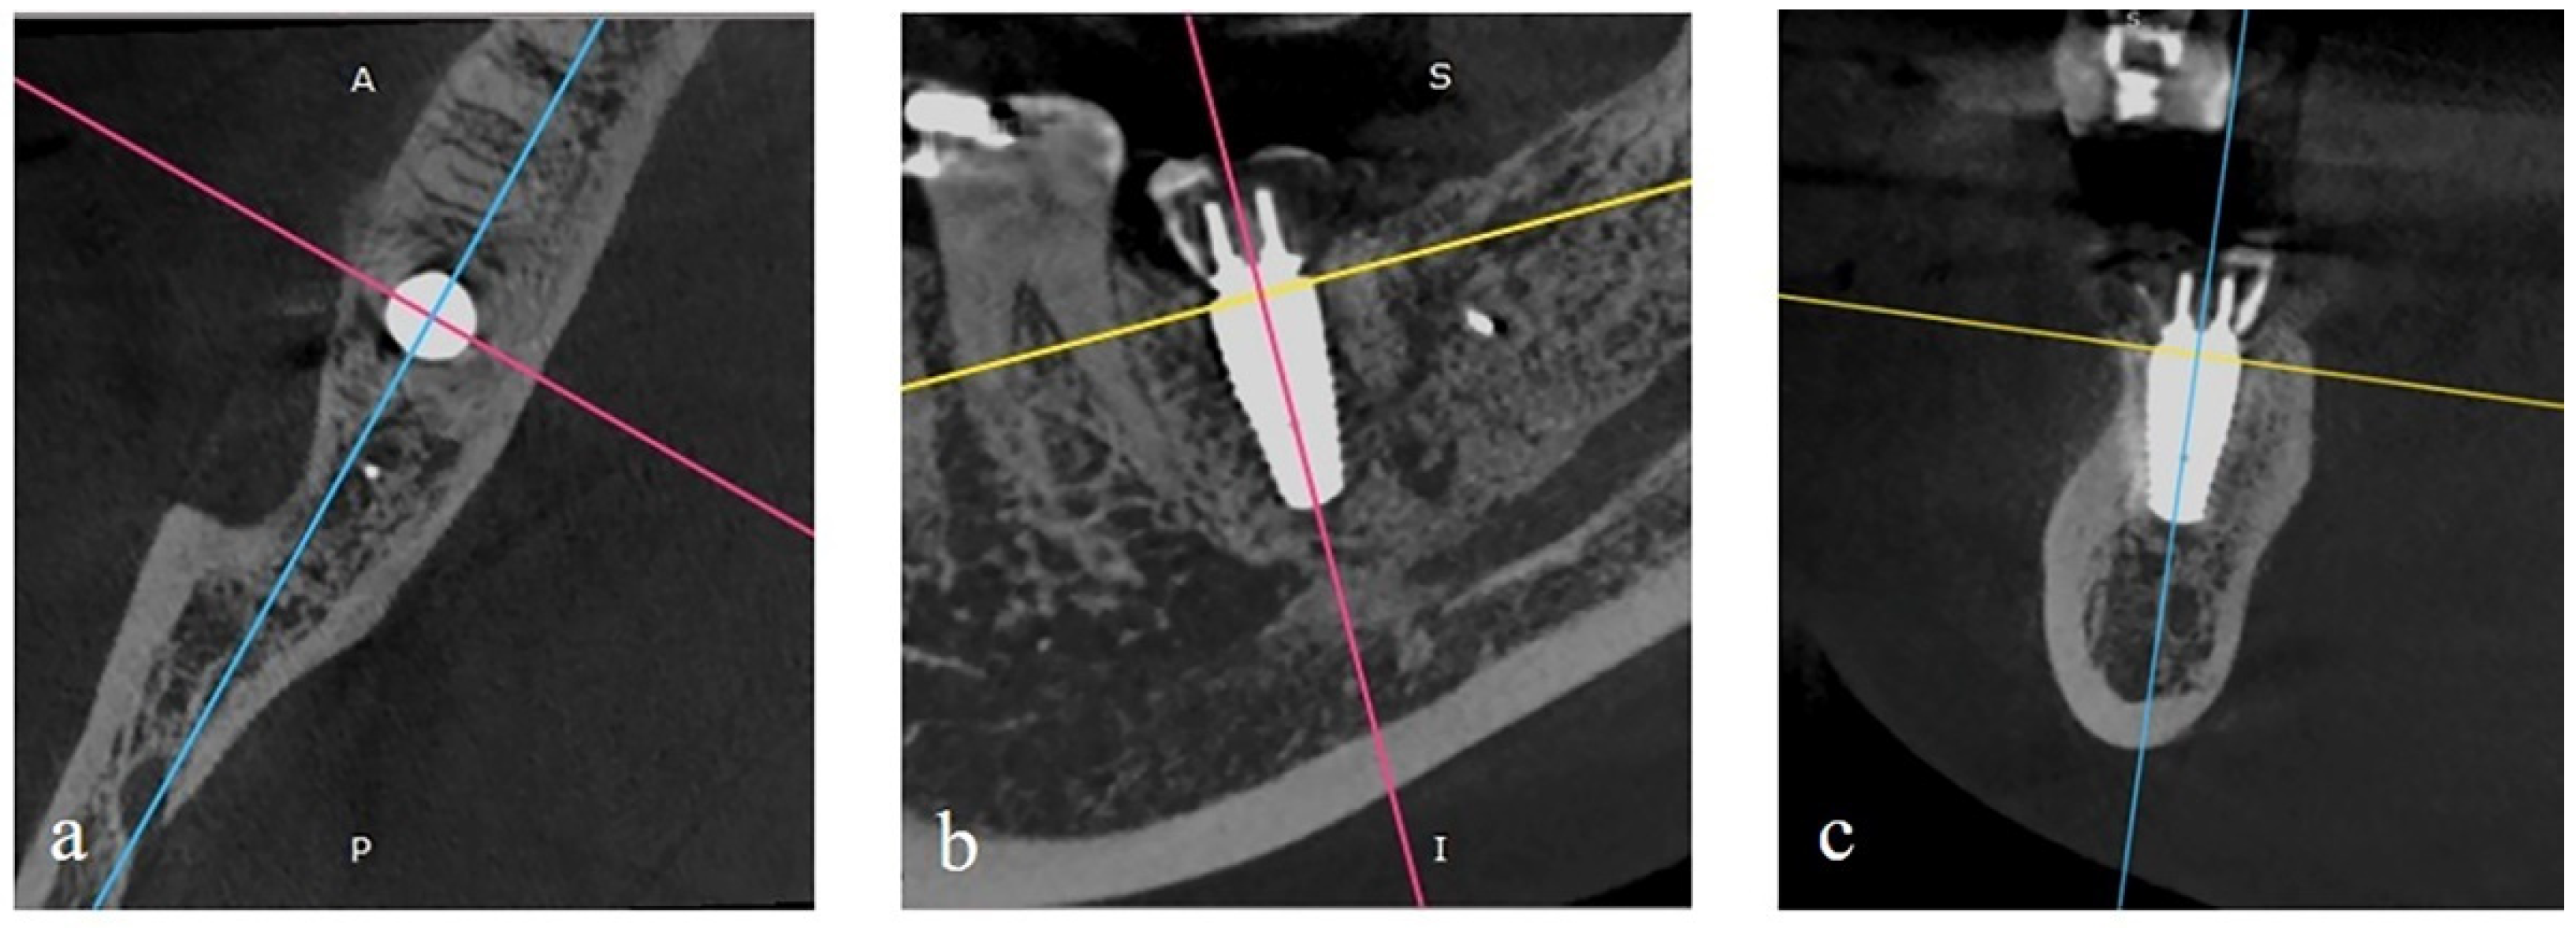

4.3. Outcome Measurement